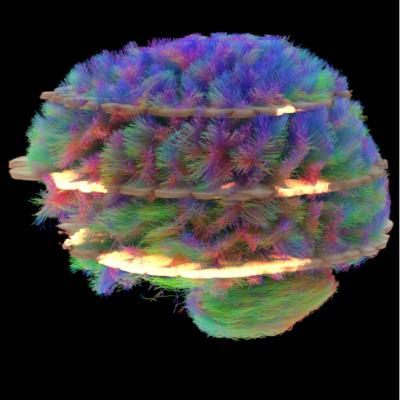

Diffusion Tensor Imaging (DTI) - Fiber Tracking - Imagilys

Diffusion Tensor Imaging (DTI) - Fiber Tracking - Imagilys

Diffusion Tensor Imaging (DTI) revealing connectivity in the brain

Diffusion Tensor Imaging (DTI) - Fiber Tracking - Imagilys

Using Diffusion Tensor Imaging (DTI), axonal fiber tractography

Diffusion Tensor Imaging (DTI) – Department of Medical Physics

Diffusion tensor imaging and fiber tractography | Radiology

DTI Animation by @neuroscience_hub on instagram